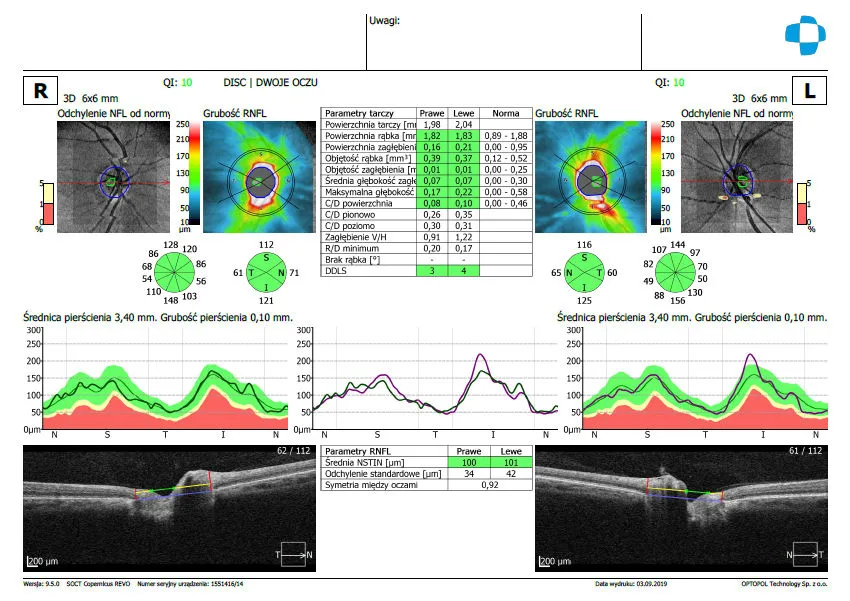

Jaskra to podstępna choroba, która często rozwija się bezobjawowo, prowadząc do nieodwracalnej utraty wzroku. OCT odgrywa tu kluczową rolę, umożliwiając wczesne wykrycie zmian. Badanie pozwala na precyzyjną ocenę tarczy nerwu wzrokowego, grubości warstwy włókien nerwowych siatkówki (RNFL) oraz kompleksu komórek zwojowych (GCC). Ubytki w tych strukturach mogą świadczyć o rozwijającej się jaskrze, zanim pacjent odczuje jakiekolwiek pogorszenie widzenia. Regularne badania OCT są zatem nieocenione w monitorowaniu pacjentów z podejrzeniem jaskry lub już zdiagnozowaną chorobą.

Grubość siatkówki i warstwy włókien nerwowych (RNFL) kluczowe parametry w diagnostyce

Wśród wielu parametrów analizowanych w wynikach OCT, kluczowe znaczenie ma grubość siatkówki, szczególnie w obszarze plamki żółtej, oraz grubość warstwy włókien nerwowych siatkówki (RNFL) wokół tarczy nerwu wzrokowego. Zmiany w tych parametrach są niezwykle ważne w diagnostyce jaskry, AMD, obrzęku cukrzycowego i wielu innych schorzeń. Analiza tych danych pozwala nam ocenić stopień uszkodzenia i monitorować skuteczność leczenia.

OCT tarczy nerwu wzrokowego (obejmujące analizę warstwy włókien nerwowych siatkówki RNFL oraz kompleksu komórek zwojowych GCC) skupia się na ocenie nerwu wzrokowego. Jest to badanie niezastąpione w diagnostyce i monitorowaniu jaskry, gdzie uszkodzenie tych struktur jest kluczowym elementem choroby.